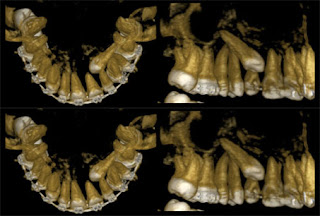

Tomografia Computadorizada Cone Beam